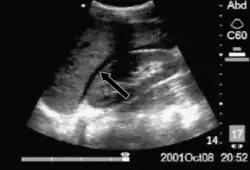

La FAST écho est plus utile chez les patients traumatisés qui sont hémodynamiquement instables. Un résultat FAST positif est défini par l'apparition d'une bande sombre ("anéchogène") dans les zones dépendantes du péritoine. Dans le quadrant supérieur droit, cela apparaît généralement dans l'espace de Morison (entre le foie et le rein droit). Cet emplacement est le plus utile car c'est l'endroit où le liquide s'accumulera avec un patient en décubitus dorsal. Dans le quadrant supérieur gauche, le sang peut s'accumuler n'importe où autour de la rate (espace périsplénique). Dans le bassin, le sang s'accumule généralement derrière la vessie (dans l'espace rectovésiculaire). Un résultat positif suggère un hémopéritoine; souvent un scanner sera réalisé si le patient est stable[20] ou une laparotomie s'il est instable. Chez ceux qui ont un résultat FAST négatif, une recherche de sources de saignement extra-abdominales peut encore être nécessaire.